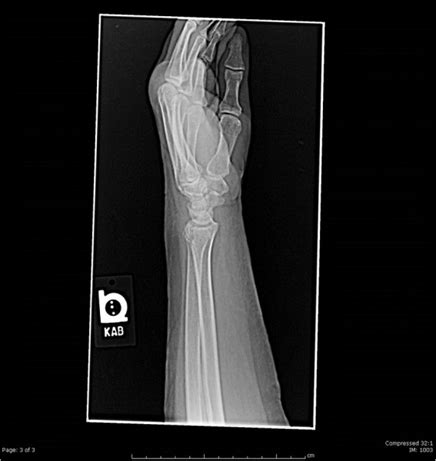

Salter-Harris type I fracture of the distal radius in a ...

Salter-Harris type I fracture of the distal radius in a ... from www.researchgate.net